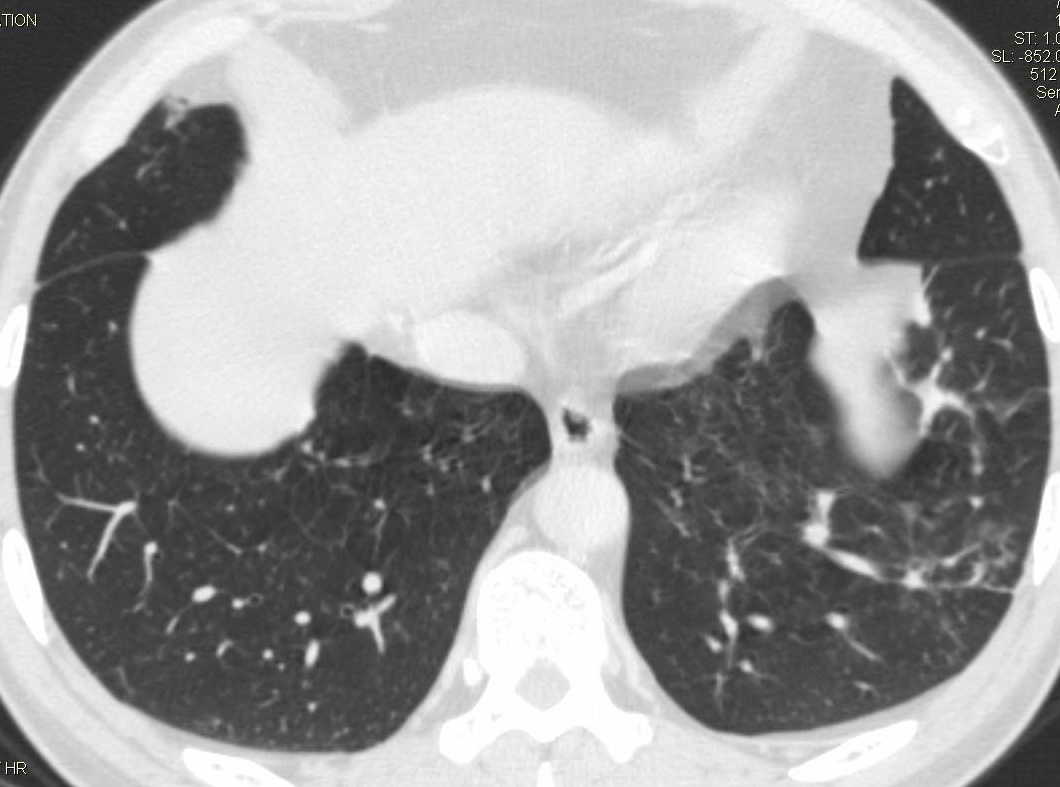

标题: CT15857:男性 58岁 咳痰带血 无发热 请各位大侠发表一下意见 [打印本页]

标题: CT15857:男性 58岁 咳痰带血 无发热 请各位大侠发表一下意见

两肺下叶肺纹理增多、增粗并呈“树芽状”改变。支气管扩张呈囊状,部分呈柱状改变。其周围可见散在的斑片样及条索样密度增高影,右肺下叶近叶间胸膜可见一形态不规则的高密度结节影,并与胸膜粘连。

考虑:支扩并发感染。

双肺多发炎性病灶,结核可能性大,建议抗炎治疗复查.右肺下叶前基底段结节灶,高度警惕肺癌可能

双肺间质性改变(间质纤维化?)伴支扩。右肺下叶有毛刺的小结节,考虑周围型肺癌可能性。